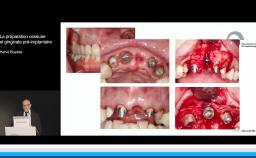

Il est communément admis qu’une épaisseur minimale de gencive kératinisée autour des implants est favorable au résultat esthétique mais aussi au maintien d’une bonne santé des tissus péri-implantaires au long terme, mais il n’existe pas de consensus à ce niveau. Une épaisseur osseuse de 2 mm autour des implants est nécessaire pour prévenir les résorptions osseuses et pour soutenir de façon pérenne les tissus mous.

- d’identifier les situations où une étape d’augmentation des tissus mous et/ou des tissus durs est nécessaire avant la mise en place de l’implant pour obtenir un résultat esthétique pérenne